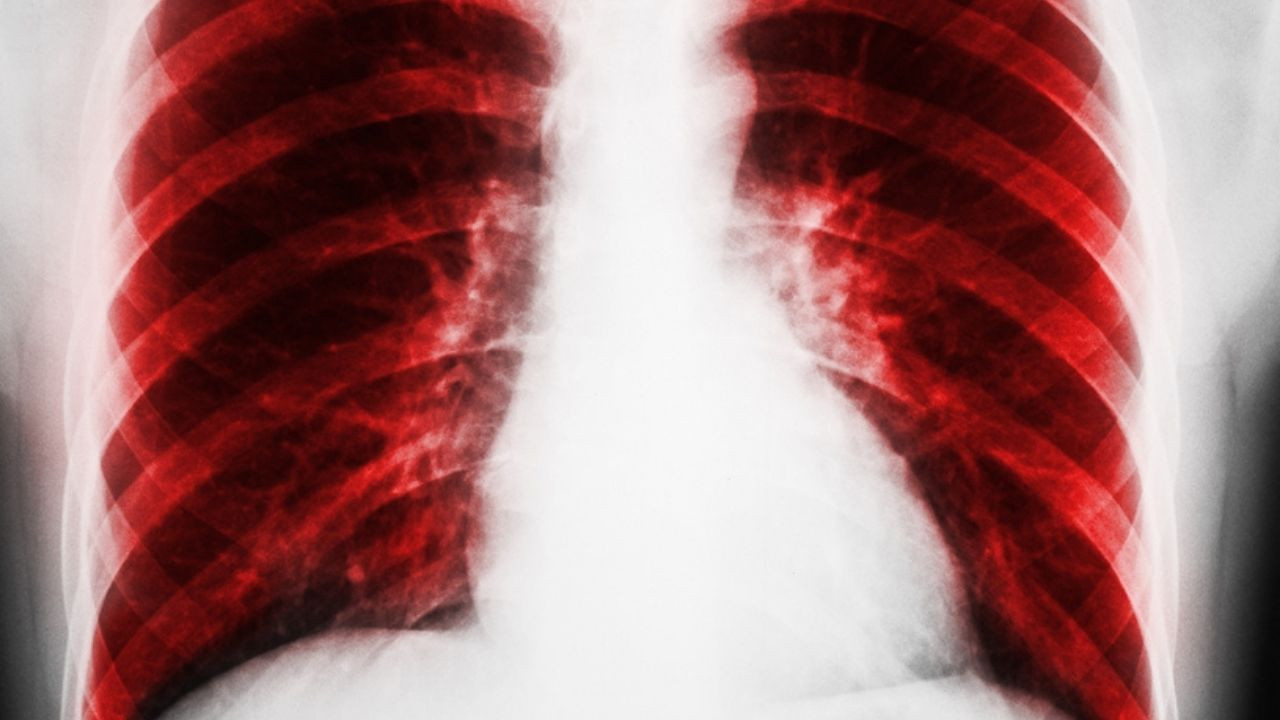

Avustralya'daki Monash Üniversitesi ile İngiltere'deki Cambridge Üniversitesi'nden araştırmacılar, kronik obstrüktif akciğer hastalığı (KOAH) ile interstisyel akciğer hastalığına (İAH) sahip kişilerin çevrimiçi şarkı söyleme terapisiyle yaşam kalitelerine artırabileceğini tespit etti.

Çalışmayı Amsterdam'daki Avrupa Solunum Derneği Kongresi'nde anlatan Profesör Natasha Smallwood, "Kronik nefes alamama durumu, KOAH ve İAH hastalarında sık görülen ve stres yaratan bir durum. Ne var ki bu semptomları kontrol altına almaya sağlayacak güvenli, etkili ve kabul edilebilir tedavi yöntemleri çok az" dedi.